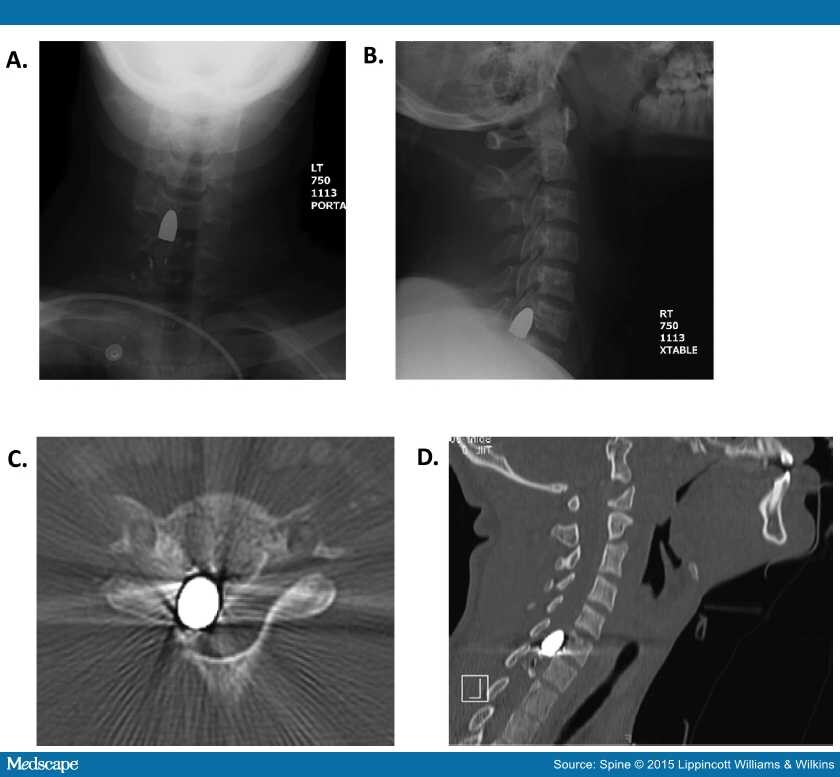

When Is Surgery Indicated for Patients with Gunshot Wounds to the Spine …

An Update on Civilian Spinal Gunshot Wounds

Cureus | Gunshot Wound to the Chest With Retained Epicardial Bullet

Complex penetrating cervical wound | Trauma Surgery & Acute Care Open

Thoracic gunshot wound | Radiology Case | Radiopaedia.org

An Update on Civilian Spinal Gunshot Wounds